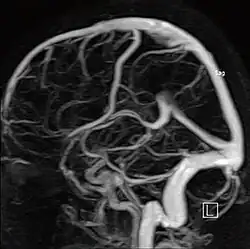

МР-ангиография

Магнитно-резонансная ангиография (МР-ангиография, МРА) — метод получения изображения кровеносных сосудов при помощи магнитно-резонансного томографа. Исследование проводится на томографах с напряжённостью магнитного поля не менее 0.3 Тл. Метод позволяет оценивать как анатомические, так и функциональные особенности кровотока.

Ангиография артерий головного мозга (времяпролётная ангиография)